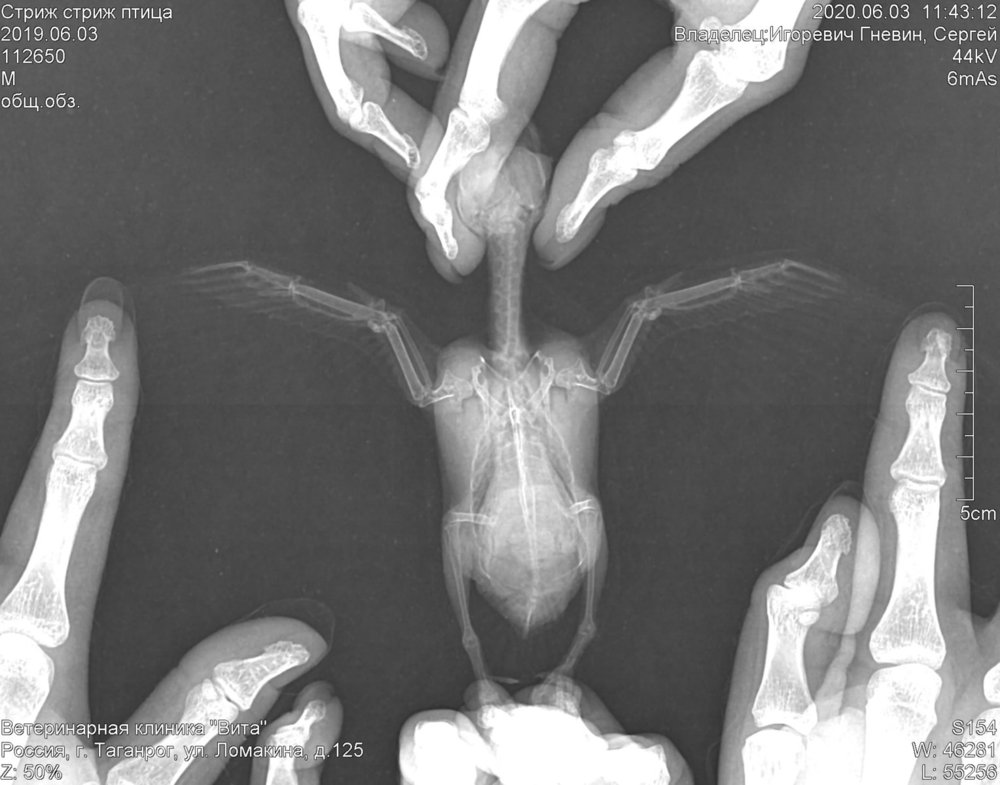

Добрый день! Вы правы. Разрыв всех мешков! Сделали рентген. Кости целые! Лечим, надеемся полетит

151AA095-A5C7-4DE0-9139-DBDCFE744537.jpeg